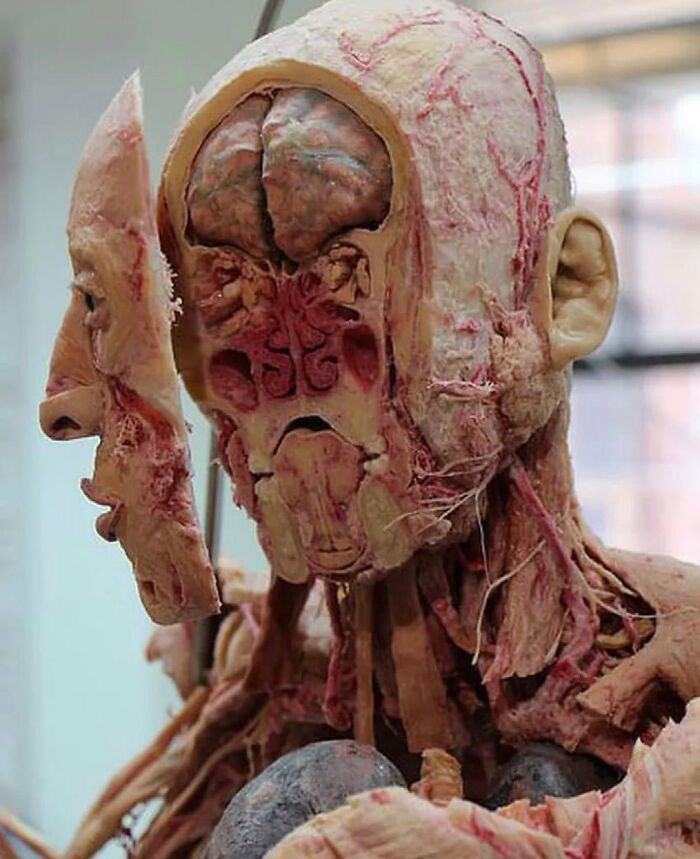

A wax model showing the anatomy of the head. It was produced in Naples by the sculptor Gennaro Ferrini between 1820 and 1830, with the wax modelled over a real skull.